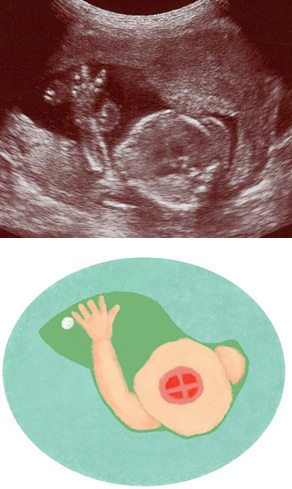

妊娠21週ころの超音波写真

心臓の機能が調べられるようになってきます

胴体の断面から心臓を見た際に、赤ちゃんの手が動いて写り込んだもの。心臓は4つの部屋に分かれています。心臓など臓器が成熟し、また、手足の動きは滑らかになってきます。